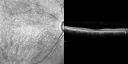

InfraRed Image - Enhanced S Cone Syndrome - Goldmann Favre - 693 views55-year-old woman while in college her vision was poor even with glasses and she sought evaluation for that. She was told after she had an electroretinogram at USF 15 years ago, that she had something with her blue cones. She does have poor night vision, but her reading vision is pretty good.

VISUAL ACUITY: OD 20/40, OS 20/40     (0 votes)

OCT Line Scan - Enhanced S Cone Syndrome - Goldmann Favre - 646 views55-year-old woman while in college her vision was poor even with glasses and she sought evaluation for that. She was told after she had an electroretinogram at USF 15 years ago, that she had something with her blue cones. She does have poor night vision, but her reading vision is pretty good.

SPECTRALIS-SD-OCT SCAN: The OCT scan does show foveal schisis in each eye with what looks like possible fluid deep to the retina, but there are some areas splitting in the right eye. There is dense retinal atrophy in each eye. There is thinning of all layers of the retina.